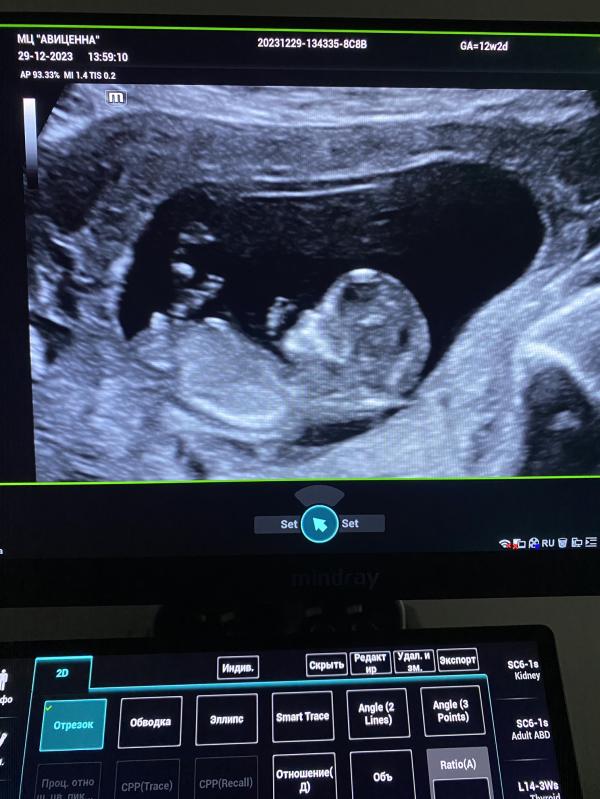

Узи показало мальчика? Делимся опытом! Скрининг и консультации: у кого тоже все сыновья?

Сегодня на плановые консультации и скрининговые узи подошли мои пациентки.

Тот случай, когда по узи все мальчики и дома сыновья.